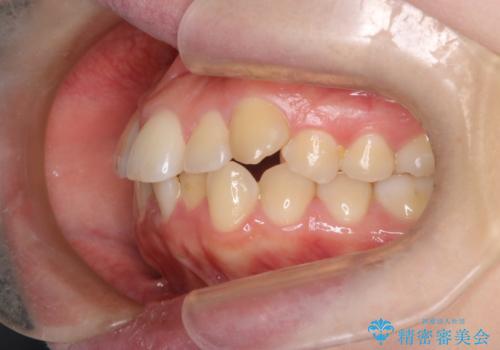

- 患者様は、結婚式までに歯並びを整えたいとのご要望で来院されました。診断の結果、上下左右の第一小臼歯を抜歯し、歯列全体を整える計画としました。審美性を重視し、目立ちにくいホワイトワイヤーを使用した矯正を提案しました。治療期間は2年を目安とし、結婚式までに前歯の整列と噛み合わせを優先的に整えるスケジュールで進めました。定期的な調整と経過観察を通じて、計画的に治療を進めました。

結婚式までに仕上げるため、通常よりも細かく調整を行い、歯の動きを効率的に管理しました。審美ワイヤーを使用したことで、治療中も目立ちにくく、写真撮影などの日常生活での見た目の負担を軽減しました。抜歯部分のスペースを閉じる際には、前歯の位置や噛み合わせのバランスに配慮し、過度な力がかからないよう進めました。患者様の大切なイベントに間に合うよう治療計画を立て、理想的な仕上がりを実現しました。